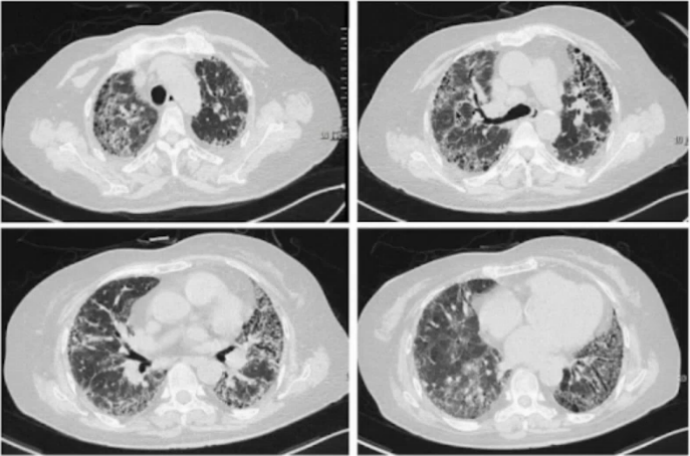

术后第23天,气管镜检查于右肺中叶开口侧壁发现瘘口(图4),考虑出现支气管胸膜瘘。术后第31天,复查胸部CT可见肺部膨胀不佳(图5)

5  复查胸部CT